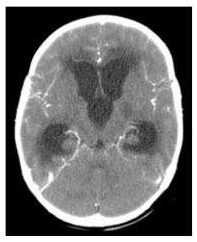

Menina de 6 anos encontra-se internada para tratamento de meningite bacteriana com ceftriaxone há cinco dias. Hoje, voltou a apresentar cefaleia holocraniana e vômitos, realizando tomografia de crânio. A conduta é

realizar derivação ventricular.